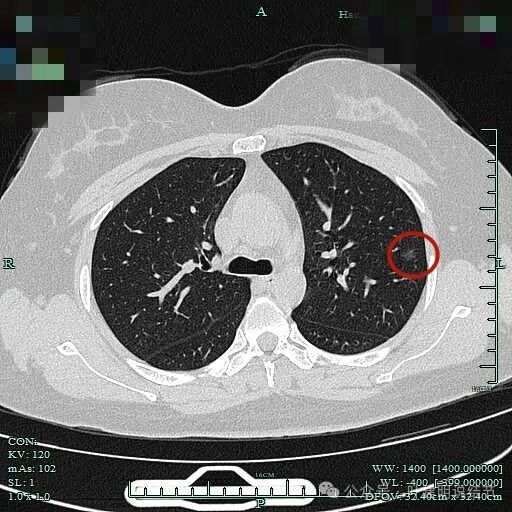

病灶出现,密度较纯,便边缘明显欠平整。